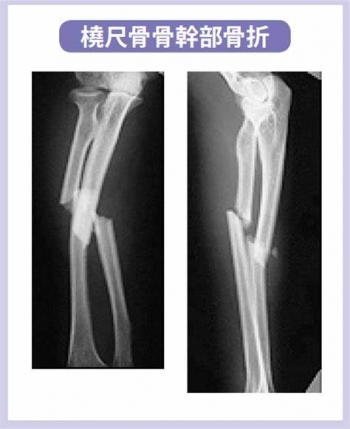

º£Æü¡¢¤´¾Ò²ð¤¹¤ë¤Î¤Ï¡¢Á°ÏÓ¹ü¹ü´´Éô¤Î¹üÀޤˤĤ¤¤Æ¤´¾Ò²ð¤·¤Æ¤¤¤­¤¿¤¤¤È»×¤¤¤Þ¤¹¡£

Á°ÏÓ¹ü¹ü´´Éô¹üÀÞ

Á°ÏÓ¹ü¹ü´´Éô¹üÀÞ¤ÎʬÎà

­£Üö¡¦¼Üξ¹ü¹üÀÞ

Üö¡¦¼Üξ¹ü¹ü´´Éô¹üÀÞ

Üö¡¦¼Üξ¹ü¹ü´´Éô¹üÀޤϡ¢Ã±ÆÈ¹üÀÞ¤è¤ê´°Á´À°Éü¤¬º¤Æñ¡£

¤½¤Î¤¿¤á¡¢¹üÌþ¹ç¤¬¿­¤Ó¤¿¤ê¡¢µ¶´ØÀá·ÁÀ®¤Î³ä¹ç¤¬¹â¤¯¤Ê¤ë

¤Þ¤¿¡¢¸å°ä¾É¤È¤·¤Æ¡¢ÊÑ·Á¼£Ìþ¡¢Á°ÏÓ²óÀû¾ã³²¡¢ÁË·ìÀ­¹´½Ì¤Ê¤É¤âµ¯¤³¤ë¤³¤È¤¬¤¢¤ê¤Þ¤¹¡£

Á°ÏӤϹüÀÞ¤·¤Þ¤¹¤È¡¢ÊÑ·Á¤¬»Ä¤ê¤ä¤¹¤¤¤Ç¤¹¤·¡¢¼ê¤Îư¤­¤Ë¤â±Æ¶Á¤·¤Þ¤¹¤Î¤Ç¡¢µ¤¤ò¤Ä¤±¤Þ¤·¤ç¤¦¤Í